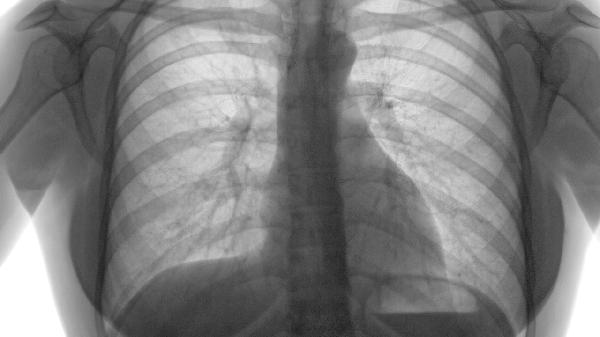

左肺舌叶纤维灶是什么意思

左肺舌叶纤维灶通常是指肺部影像学检查中发现的局部纤维化病变,可能由肺部感染、结核愈合后遗留或慢性炎症刺激导致。纤维灶属于陈旧性病变,多数无需特殊治疗,但需定期复查以排除活动性病变。